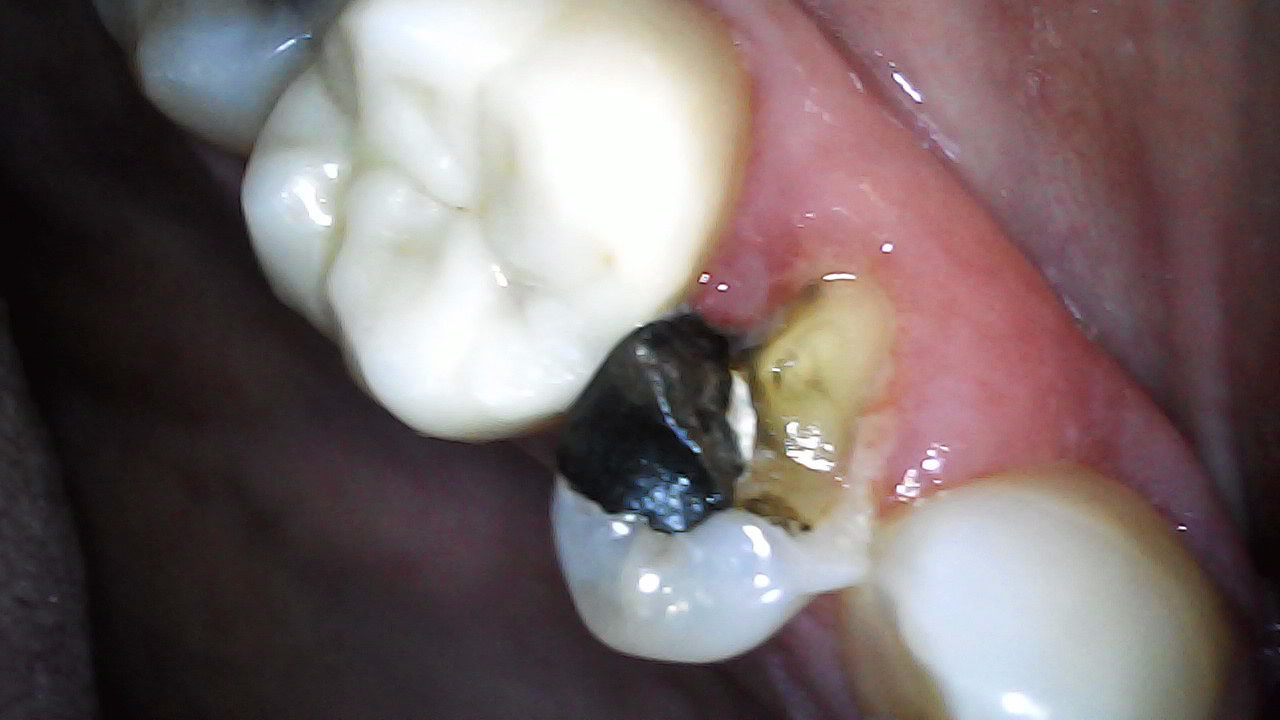

15 Fractured Buccal cusp